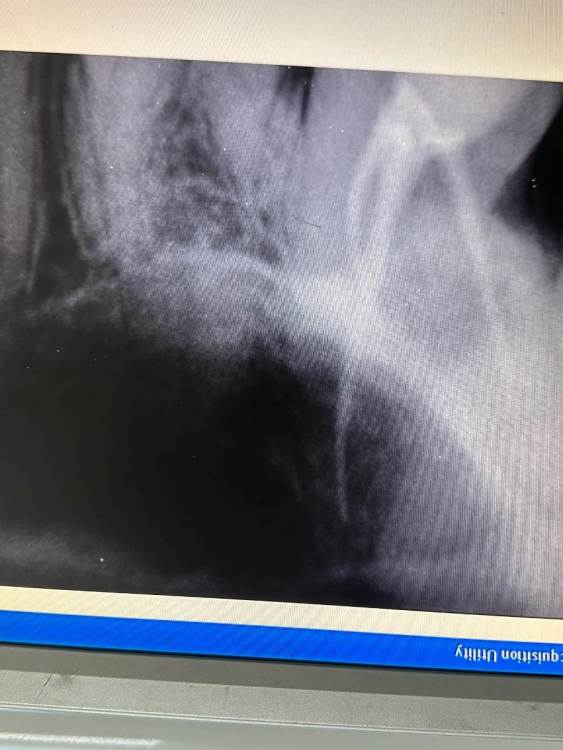

Здравствуйте!16 дней назад пролечили 7 верхний зуб. Сразу после началась сильная боль, которая держалась 2 дня и потом пошла на спад. На 7 день она остановилась и держится на одном месте. Зуб реагирует когда постучишь по временной пломбе. Когда поешь, потом начинал ныть. Так же легкие, редкие распирающие и пульсирующие боли. На зуб Накусывать неприятно. Несколько раз ломило от него все зубы, а до него было больно даже языком дотронуться.  В легком дискомфорте все это сохранялось 7 дней. На 13 день доктор распломбировала каналы, зуб поболел после распломбировки день, после вмешательства, как все утихло  и опять  я чувствую тот же дискомфорт, т е после распломбировки каналов ничего не изменилось, все держится на одном месте. сейчас в каналах кальций.Возможно ли что каналы зря распломьировали?  И проблема не в них. При удалении нерва доктор сказал, что кровь из канала не останавливалась, но потом промыла вроде остановилась и она его запломбировала.

Здравствуйте, скорее всего дело в четвертом канале, который пропустили(не нашли) и не обработали.  Сделайте КТ,  там видно будет,  что с четвертым каналом.